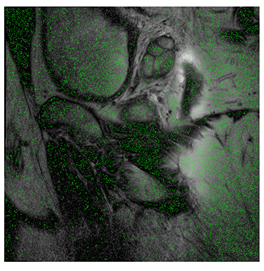

4.3. The Results

In this subsection, we describe three experiments used to measure the performance of the proposed method. The first experiment shows the stegoimage and marks the pixels’ positions that have been modified during the embedding process, as shown in Table 2, Table 3, Table 4, Table 5, Table 6 and Table 7. To make modified pixel positions have a pronounced effect, we set bpp (bit per pixel) rate at 0.05 and 0.025. It can be seen from the results that the proposed local complexity function can distinguish ROI and RONI from most of the medical images, so modified pixels are mainly gathered in RONI. However, it is observed that the proposed local complexity function cannot distinguish between ROI and RONI in the Prostate-MRI database due to the relative complexity of the image. Besides, “Modified BPP” represents the proportion of pixels in the image that have been modified. We observed that the performance of “baboon” in the grayscale standard images database is poor because that image’s pixels are relatively complex. It becomes challenging to select the more embeddable pixels based on the proposed local complexity function. Nevertheless, the modified pixel positions in other grayscale standard images, such as Lena and Barbara, are relatively smooth, verifying that our local complexity function is also applicable to general images.